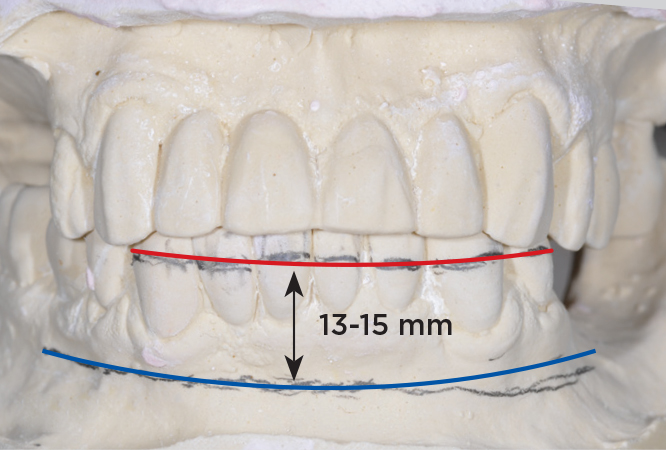

Fig 5. Bone reduction model surgery performed in mandibular arch to create 13 mm to 15 mm of inter-occlusal space required for the mandibular All-on-4 provisional restoration.

Figure 5

An important advantage of this approach is the ability to simulate bone reduction on the models and verify the presence of 15 mm to 17 mm and 13 mm to 15 mm of required inter-occlusal space for maxillary and mandibular restorations, respectively. This creates a platform for a diagnostic wax-up of the proposed dental rehabilitation and fabrication of wax prosthesis try-ins when necessary. Finally, a modified All-on-4 provisional prosthesis surgical and restorative guide developed by the authors for restoration-driven surgery and simplified restorative procedures is fabricated (Figure 2 through Figure 8).